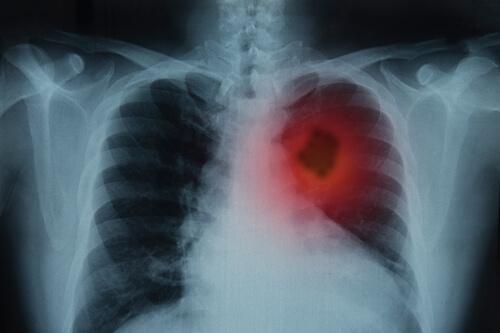

Jos nämä oireet jatkuvat yli kolmen viikon ajan, on hyvin tärkeää käydä lääkärissä ja tehdä rinnan röntgenkuvaus. Tuloksiin perustuen lääkäri voi pyytää tietoja terveydestäsi, tehdä perustutkimuksen sekä teettää laboratoriokokeita.

- Kuvantaminen: Näin lääkäri voi saada kuvia kehon sisäisistä alueista.